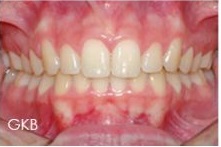

Mesmo caso após a cirurgia no tempo oportuno

O tratamento do freio hipertrófico é cirúrgico e a época mais oportuna para este procedimento é quando os caninos apresentarem-se pelo menos com a metade de suas respectivas coroas expostas na cavidade bucal. A força eruptiva, neste momento clínico, favorece o fechamento do diastema.